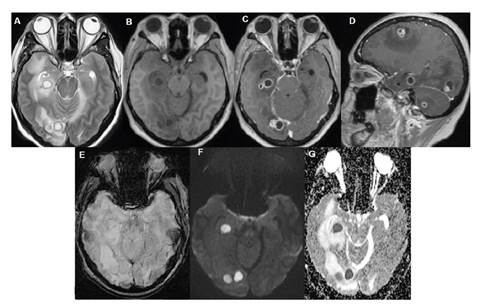

La fiebre disminuyó hasta los 39 °C y el examen neurológico evidenció compromiso del tercer par craneano derecho, sin signos de irritación meníngea u otras alteraciones, por lo que se le practicó una resonancia magnética cerebral simple con contraste, la cual evidenció múltiples lesiones en el parénquima cerebral con edema vasogénico asociado (figura 2).

Ante dichos resultados y dada la persistencia de la cefalea, la fiebre y el compromiso del tercer par craneano derecho, se tomó una biopsia de una de las lesiones cerebrales y se sometió a estereotaxia, con lo cual se halló infiltrado inflamatorio; el cultivo fue positivo para Nocardia spp. a los tres días de incubación. Se inició el tratamiento antibiótico con trimetoprim-sulfametoxazol (300 mg/1.500 mg cada 8 horas) y 1 g de ceftriaxona por vía intravenosa cada 12 horas, el cual fue tolerado adecuadamente por la paciente y tuvo mejoría clínica: disminución progresiva de la cefalea, ausencia de fiebre, resolución de leucocitosis y mejoría de las lesiones evidenciada en la resonancia magnética nuclear cerebral de control.

El control con resonancia magnética a los siete meses del tratamiento con trimetoprim-sulfametoxazol evidenció una disminución del número de las lesiones, así como de la reacción inflamatoria en torno a estas. Por ello, en el momento de la elaboración de este reporte, se cambió la administración de trimetoprim-sulfametoxazol a la vía oral y una dosis de 320 mg/1.600 mg cada 8 horas, para completar 12 meses de tratamiento.